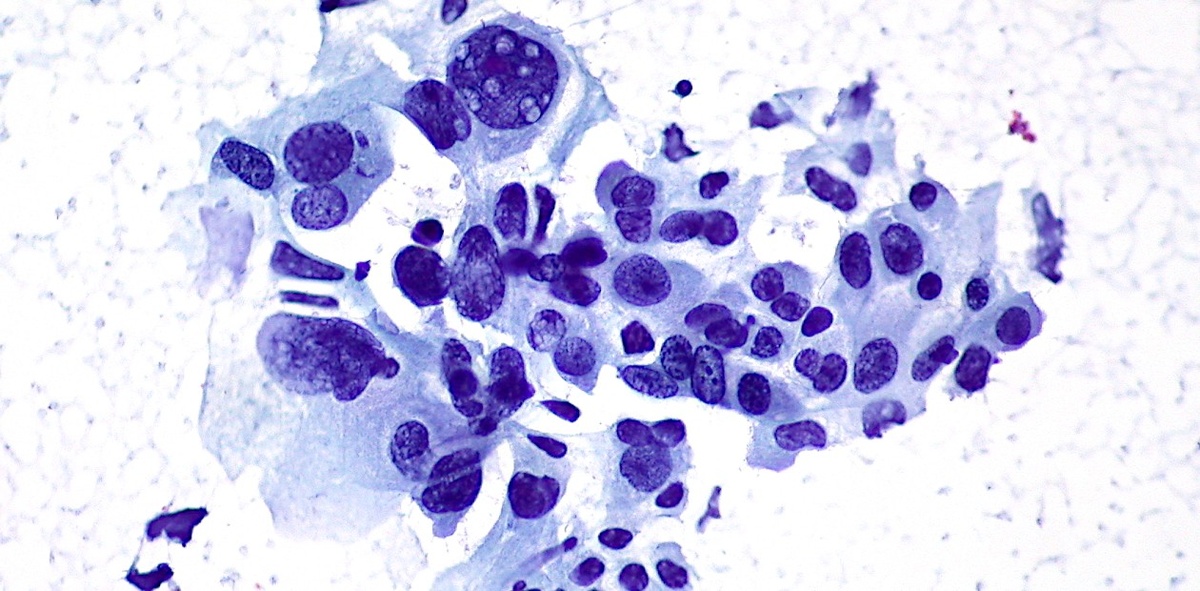

Немелкоклеточный рак легкого